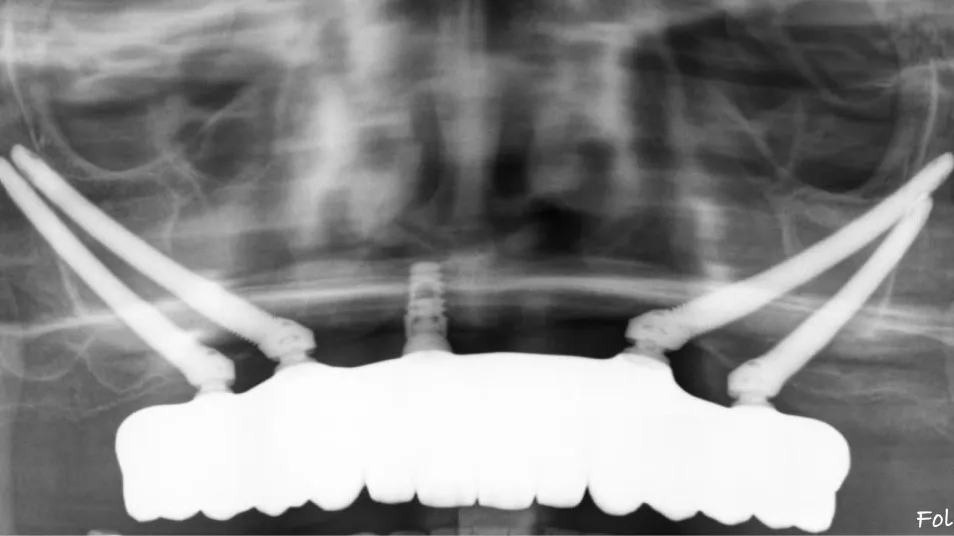

Behind every restored smile, there is precise planning. These radiographic studies show how advanced imaging and implant techniques allow us to transform even the most complex cases into stable, long-term solutions.

Our innovative techniques, including zygomatic and pterygoid implants, anchor directly into your natural bone structure, creating a strong and lasting foundation for fixed, beautiful teeth — even in the most complex cases.

Custom Subperiosteal Implants

When the mandible and maxilla are too resorbed to support conventional dental implants, a custom titanium framework is the solution.